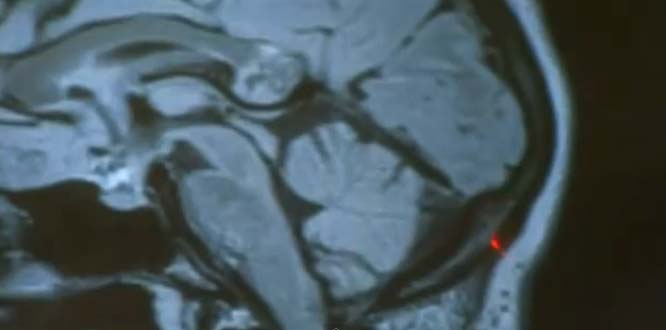

在鑽孔手術後,醫生在她大腦當中發現了畸胎瘤 (teratoma)!

During keyhole surgery, Shahinian discovered a teratoma, also known as an embryonic twin, in Karanam’s brain.

畸胎瘤是一種的卵巢腫瘤,裡頭也時常能看見一些器官組織,如同毛髮、骨頭、牙齒、肢體、軟骨等等。

26歲的雅米妮還開玩笑地說:「這就像是個『邪惡的雙胞胎』,而你敢相信這已經折磨了我26年嗎?」她也說在發現腫瘤之後,自己跟這個「雙胞胎腫瘤」好像也莫名有種情感上的連結。

醫生現在也已經移除畸胎瘤,也預計雅米妮能夠完全康復。